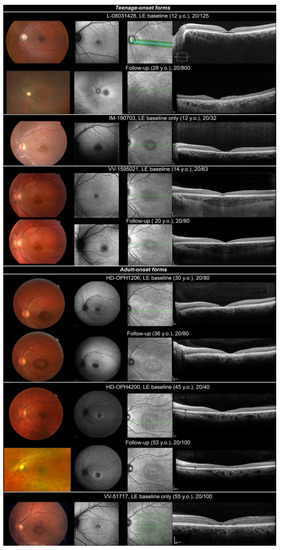

| Teenage-onset forms | |||||||||||

| L-08031428, M | 12 | VA loss, poor colour discrimination and photophobia | 20/125 OU | Cyclopleged +1.25 (−0.50) 155° RE +1.75 (−0.75) 30° LE | Temporal pallor of ONH Arteriolar narrowing Punched-out round foveal lesion with hyperpigmented edges | Severe without-axis dyschromatopsia on Lantony D-15 | Small relative central scotoma on static VF; Kinetic VF normal to all target sizes | Cone–rod dysfunction Reduced b/a ratio in DA 3.0 ERG | Round foveal hypoAF lesion | Foveal outer layer cavitation | CORD |

| IM-190703, M | 12 | VA loss, reading difficulties | 20/32 OU | (−0.75) 90° RE −0.75 (−0.5) 90° LE | Temporal pallor of ONH Punched-out round foveal lesion with hyperpigmented edges | NA | Central scotoma | Scotopic normal Photopic reduced to 1/3 normal limits | Round hypoAF lesion | Loss of foveal outer reflective layers (ONL, EZ and RPE) | COD |

| VV-1595021, F | 14 | VA loss, reading difficulties, photophobia | 20/40 OU | +0.75 OU | Punched out round foveal lesion with hyperpigmented edges | Ishihara normal | 10° relative central scotoma at I1e target on static VF | Scotopic/photopic within normal limits | Round hypoAF lesion | Foveal outer layer cavitation | MD |

| Adult-onset forms | |||||||||||

| HD-OPH1206, M | 30 | VA loss, photophobia (especially outdoors), contrast issues | 20/63 RE 20/80 LE | −0.25 (−0.50) 170° RE −0.50 (−0.25) 80° LE | Punched-out round macular lesion with hyperpigmented edges | Severe without-axis dyschromatopsia on Lantony D-15 | 5° relative central scotoma at I1e target on static VF | Scotopic within normal limits Photopic reduced | Round hypoAF lesion with watershade edges | Loss of macular outer reflective layers (ONL, EZ and RPE) | COD |

| HD-OPH4200, F | 37 | VA loss, reading difficulties, asthenopia, reduction in contrast sensitivity | 20/50 RE 20/32 LE | −1.75 (−0.25) 177° RE −2.00 (−0.25) 159° LE | Temporal pallor of ONH Loss of foveal light reflex | Red–green dyschromatopsia with the Farnsworth 100 Hue | 5° relative central scotoma at I1e target on static VF | Scotopic within normal limits Photopic reduced | Round hypoAF lesion, surrounded by hyperAF edges | Loss of macular outer reflective layers (ONL, EZ and RPE) | COD |

| VV-51717, M | 55 | VA loss, reading difficulties, photophobia | 20/100 OU | −0.50 (−0.50) 0° RE −0.75 (−0.50) 0° LE | Temporal pallor of ONH, Punched-out round macular lesion with hyperpigmented edges | Ishihara normal | NA | Scotopic/photopic within normal limits | Round hypoAF lesion, surrounded by hyperAF edges | Loss of macular outer reflective layers (ONL, EZ and RPE) | MD |